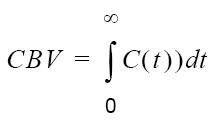

| CBV |  |  |

| table legend | p = density of brain tissue R(t) = Residue function kH = correction factor | |

Relative Blood Volume

Relative Blood Volume (rCBV) describes the blood volume of the cerebral capillaries and venules (not arteries) per cerebral tissue volume.